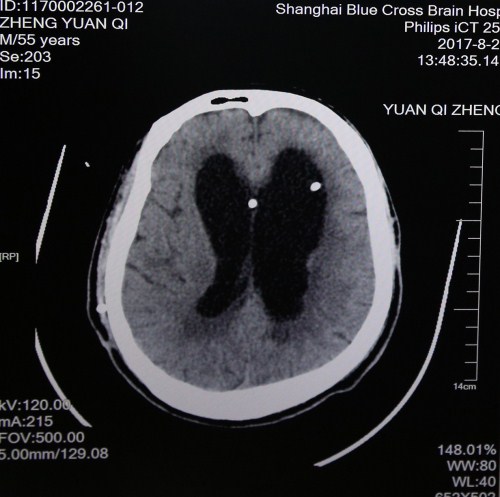

最近头颅CT影像:脑沟回明显,脑室缩小,脑压降低,重新置管分流后有效

但郑元齐每天傍晚会发烧,经会诊查到之前置入的脑室-腹腔分流管腹腔段阻塞、腹壁出现化脓,脑脊液混浊,肺部感染,而且有低压性脑积水,情况不乐观,随即决定重新置管,转入神经外科。5月8日,神经外科主任医师、博士研究生导师、沈建康教授亲自为郑元齐撤出原来的分流管,安置omaya囊,每日引出感染的脑脊液,5月30日脑脊液完全正常后又为郑元齐重新分流。术后,郑元齐颅内感染、反复高热等情况明显好转。